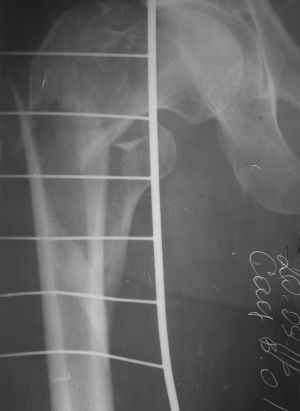

Чрезвертельный перелом правого бедра

Пациент 64 лет, поступил к нам 20.09.11. Сбит автомобилем. Сейчас на скелетном вытяжении. На КТ видно раздробленность черезвертельной зоны в саггитальной плоскости и вовлеченность шейки. Гамма? LCP?